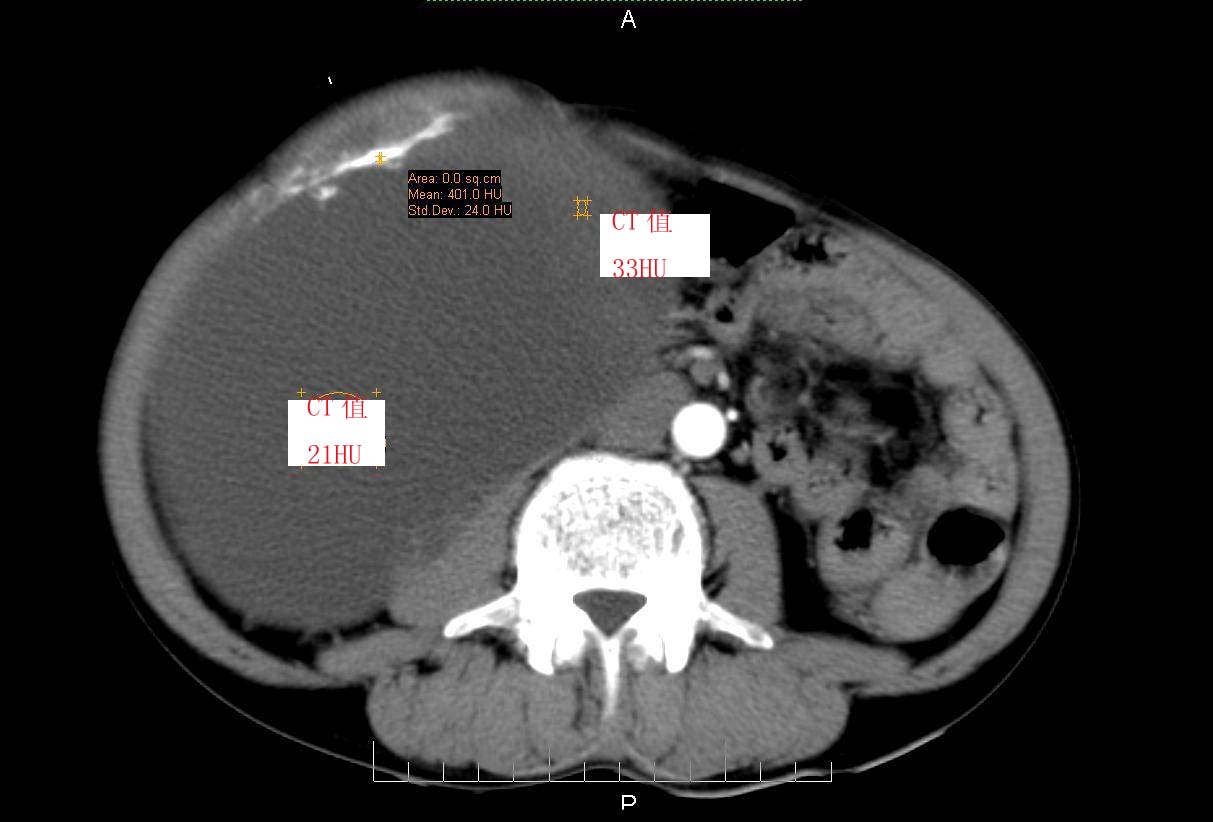

男性 60岁,腹部肿块4年余,肿块逐渐增大,活动性差,无血尿。

平扫

ct值测量

考虑肾囊肿并囊内出血。

囊性肾癌可能性大

右侧多发性肾囊肿,其中之一巨大(不排除其为重复肾积水可能);右肾积水。

考虑右肾多发囊肿并出血

右肾脏巨大囊样影、囊壁有钙化,囊样影轻度强化有软组织成份。不除外畸胎瘤可能。

囊性肾癌可能性大,右肾多发囊肿。

巨大囊性肿块,囊壁较厚有强化,有团片状钙化,病灶内下方灶内见片絮状高密度影,增强有轻中度强化,考虑囊性肾癌可能性大

右肾上部巨大的囊实性影,实性部分轻度强化。壁有钙化。考虑右肾囊腺癌。右肾盂积水。

定位;肾明显与病灶杯口相交,可以肯定病变来自右肾。

定性;病灶囊性为主,前下部含实性成分,及钙化,部分壁厚薄不均。

肾囊实性病变有;1,囊性肾癌2,囊性肾瘤。3,复杂囊肿。4,重复肾伴积水。然2、3壁相对规则。

综上考虑;囊性肾癌》重复肾伴积水。